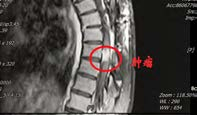

患者李女士(化名)来自西北少数民族地区,罹患胸段椎管内脊膜瘤,此前已在当地医院历经两次手术。近日,患她再次出现行走困难、疼痛难以平卧以及大小便费力,偶有失禁等症。患者首先回到最初就诊的省级医院,胸椎MRI示肿瘤再度复发,鉴于再次手术的难度和风险过高而被建议转院治疗。

几经辗转,患者来到我院神经外科就诊。郭振宇副主任医师接诊后,详细了解病情,发现“因多次手术,造成肿瘤与神经组织粘连严重,并且椎管腔内外解剖结构不清,再次手术患者瘫痪风险很高,并有可能大小便失禁”。